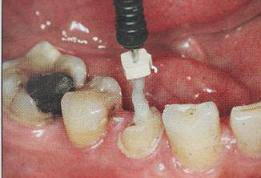

必要的情况下先开阔根管口建立一定的视角后,慢速手机上G钻为引导钻,由号递增引导开阔通路;P钻预备桩道,同样需要由小向大号递增,直到选择好适合的号预备到规定测量的深度即可,再配合纤维桩系统中各型号纤维桩所匹配的桩道钻,预备、修整成与纤维桩相适应的桩道。

预备后根管壁上会不同程度的牙胶和封闭剂等残留物,所以桩道预备前后建议X线片辅助检查预备深度等情况,而残留物也会很清晰地显现。